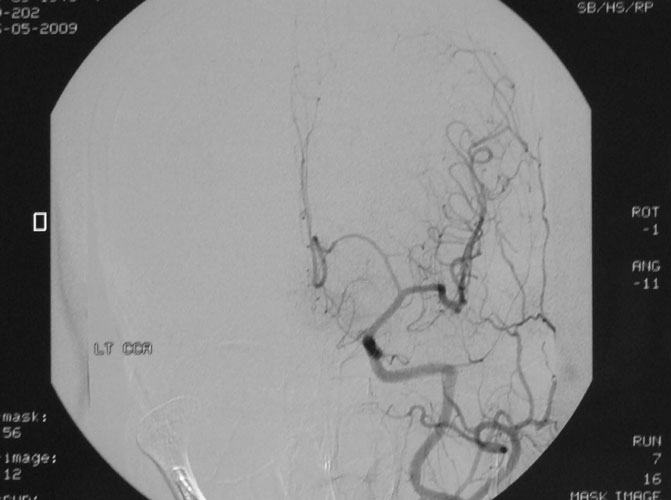

Aneurysms

Aneurysms are balloon-like outpouchings from an intracranial artery, that can rupture and present as subarachnoid hemorrhage. SAH constitutes an emergency, and if severe can be life threatening. Management is early diagnosis by brain imaging and cerebral angiography, followed by definitive treatment in the form of surgical clipping or endovascular coiling.

Arteriovenous malformations

Arteriovenous malformations of the brain are abnormal bunch of blood vessels that can rupture causing bleeding, or may cause seizures. Brain imaging (CT, MRI) is required for early diagnosis, while definitive treatment is carried out after cerebral angiography. Treatment implies craniotomy and excision of the AVM, which can be done safely in majority of the cases. Embolisation and radiosurgery are acceptable substitutes, but carry risk of further bleeding.